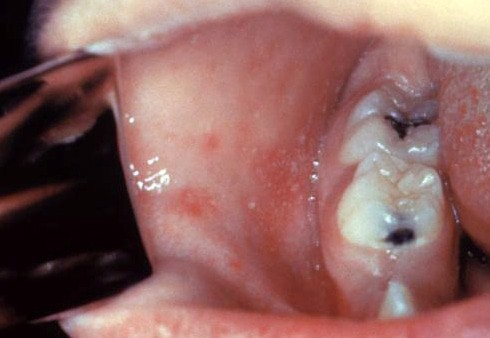

- On day 1-3, your child may experience up to four days of high fever often greater than 40C (104.0F), and a severe, brassy cough, runny nose, conjunctivitis. The classic sign of measles: the nose and eyes run continuously. You may also notice blue-white spots with a red halo appear inside the mouth.